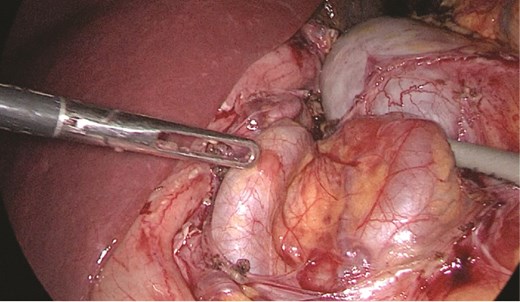

Multidisciplinary discussion was held to evaluate the most appropriate course of action for the patent condition, and the consensus was reached to pursue embolization as a first intervention. Embolization was performed by interventional radiology with no complications post-procedure, and the patient was optimized prior to her procedure. Patient was taken to the operating room in stable conditions. The spleen was enlarged around 20 cm. Inferiorly, the omentum and part of the transverse colon was attached to the spleen (Fig. 3), so we freed the omentum from the splenic tissue. The dissection continued until reaching short gastric vessels and entering the lesser sac (Fig. 4). Once the lesser sac was entered, the splenic vessels were identified (Figs 5 and 6), the splenic vein was hugely dilated with multiple collateral branching vessels at the hilum. Gaining posterior mobilization of the vein was challenging. The splenic artery was tortuous from the insertion around itself (Fig. 7). After complete mobilization of the fundus, we elected to divide each vessel starting with the splenic artery so we can achieve full mobilization of the vein (Fig. 9). After controlling the splenic artery, the splenic vein was dissected proximal to the splenic hilum (Fig. 8). It was hugely dilated and its wall is thickened secondary to AV fistula. It was difficult to achieve circumferential dissection, so we decided at that moment to convert to laparotomy to complete ligating the vein and to retrieve the specimen (Fig. 10a and b).

The spleen inferiorly, attached to it the mesentery and the transverse colon.

Stomach attached to the medial border of the spleen. Short gastric vessels.